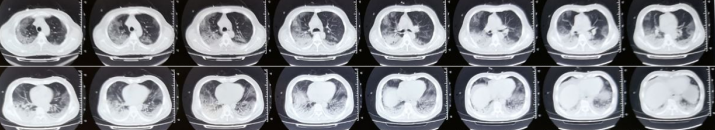

胸部CT:2021年10月21日外院胸部CT可见双肺下叶背段及基底段出现间质性改变(图1)。10月29日复查胸部CT可见双肺磨玻璃样改变较前明显加重,双侧出现少量胸腔积液(图2)

2   患者胸部CT(2021-10-29)